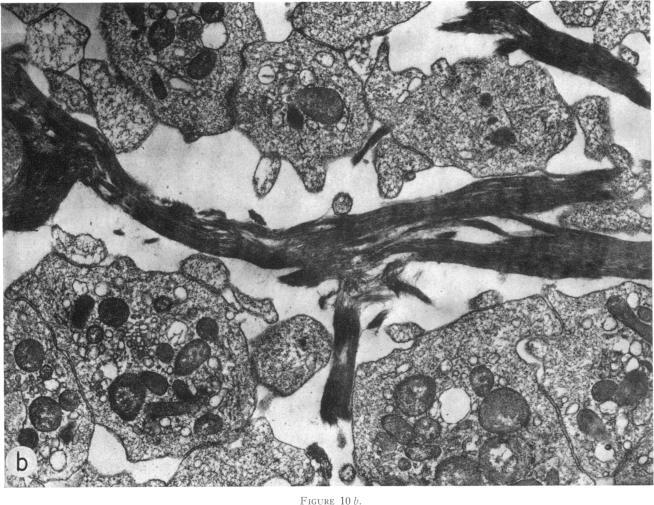

血小板与正在聚合的纤维蛋白的相互作用。

Platelet interaction with polymerizing fibrin.

Interaction of washed pig, rabbit, or human platelets with fibrinogen was studied during its transition to fibrin using photometric, isotopic, and electron microscopic techniques. Untreated fibrinogen and fully polymerized fibrin had no detectable effect on platelets. Fibrinogen, incubated with low concentrations of reptilase or thrombin, formed intermediate products which readily became associated with platelets and caused their aggregation. Neutralization of the thrombin did not prevent this interaction. In the absence of fibrinogen, reptilase did not affect platelets. The interaction of polymerizing fibrin with platelets was accompanied by small losses of platelet constituents (serotonin, adenine nucleotides, platelet factor 4, and lactic dehydrogenase). This loss did not appear to be the result of the platelet release reaction. Inhibitors of the release reaction or of adenosine diphosphate (ADP)-induced aggregation did not prevent the interaction of platelets with polymerizing fibrin. Apyrase or prostaglandin E(1) (PGE(1)) reduced the extent of platelet aggregation by polymerizing fibrin, but the amount of protein associated with platelets was slightly increased. The interaction of polymerizing fibrin with platelets was completely inhibited by ethylenediaminetetraacetate (EDTA) or ethylene glycol bis (beta-aminoethyl ether) N, N,N',N'-tetraacetic acid (EGTA).Fibers formed in solutions of polymerizing fibrin were larger in the presence than in the absence of washed platelets, suggesting that platelets affect fibrin polymerization. The adherence of platelets to polymerizing fibrin may be responsible for the establishment of links between platelets and fibrin in hemostatic plugs and thrombi.

利用光度测定法、同位素法和电子显微镜技术,研究了洗涤过的猪、兔或人血小板在纤维蛋白原向纤维蛋白转变过程中与纤维蛋白原的相互作用。未经处理的纤维蛋白原和完全聚合的纤维蛋白对血小板没有可检测到的影响。与低浓度的蛇毒凝血酶或凝血酶一起孵育的纤维蛋白原形成了中间产物,这些中间产物很容易与血小板结合并导致血小板聚集。凝血酶的中和并不能阻止这种相互作用。在没有纤维蛋白原的情况下,蛇毒凝血酶不会影响血小板。正在聚合的纤维蛋白与血小板的相互作用伴随着血小板成分(5-羟色胺、腺嘌呤核苷酸、血小板因子4和乳酸脱氢酶)的少量损失。这种损失似乎不是血小板释放反应的结果。释放反应抑制剂或二磷酸腺苷(ADP)诱导的聚集抑制剂并不能阻止血小板与正在聚合的纤维蛋白的相互作用。腺苷三磷酸双磷酸酶或前列腺素E(1)(PGE(1))通过使纤维蛋白聚合减少了血小板聚集的程度,但与血小板结合的蛋白量略有增加。正在聚合的纤维蛋白与血小板的相互作用被乙二胺四乙酸(EDTA)或乙二醇双(β-氨基乙醚)N,N,N',N'-四乙酸(EGTA)完全抑制。在有洗涤过的血小板存在的情况下,在正在聚合的纤维蛋白溶液中形成的纤维比没有血小板时更大,这表明血小板会影响纤维蛋白的聚合。血小板与正在聚合的纤维蛋白的黏附可能是止血栓和血栓中血小板与纤维蛋白之间建立联系的原因。